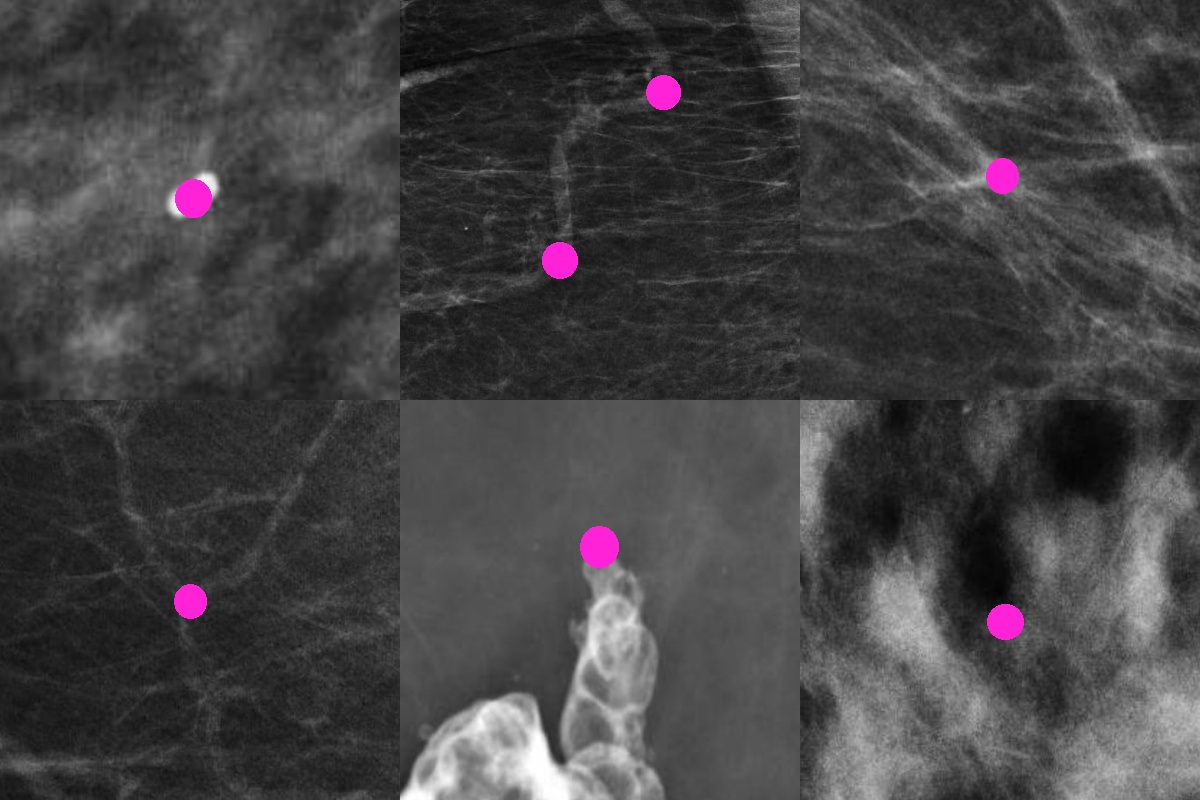

Anatomical landmarks are provided exclusively for the evaluation subset of MGRegBench, enabling quantitative evaluation of registration accuracy. These landmarks include calcifications, duct or blood vessel bends, intersections, forks, visible masses and dark or bright blobs (Fifure 4).

Refer to caption

Figure 4: Examples of anatomical landmarks used for registration evaluation in MGRegBench. Each panel illustrates a distinct landmark type manually annotated by expert radiologists: microcalcifications, bends in ducts or blood vessels, vessel or duct intersections, forks, visible masses, and dark/bright blob contours.